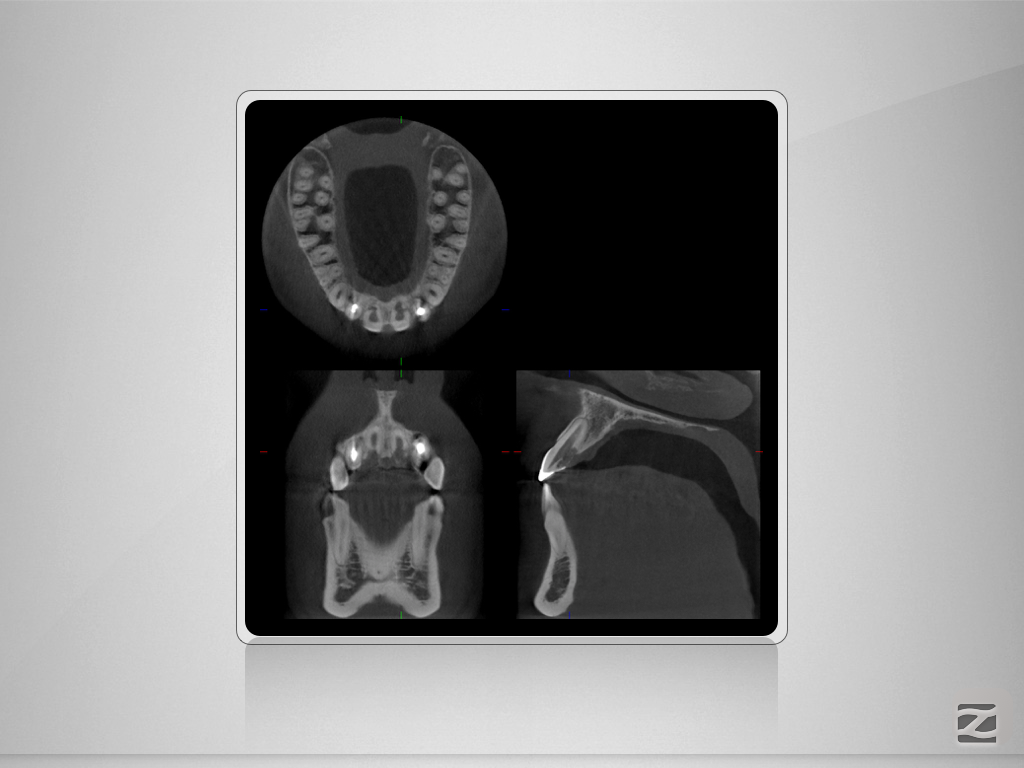

12,11 D.002

Wer hätte es gedacht , …